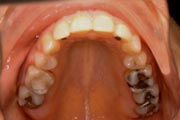

Crowding

After